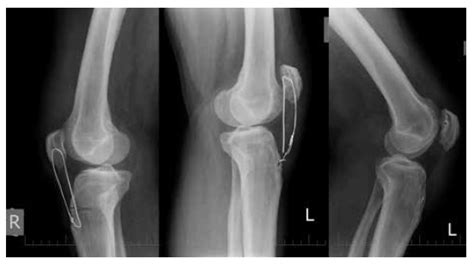

Veterinary first aid on canine fractures.